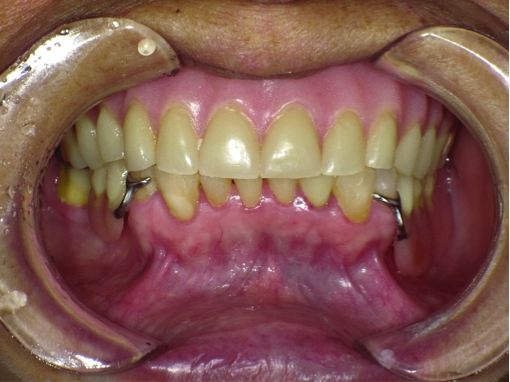

An examination revealed that her maxilla had lost a significant amount of bony support, leaving a relatively flat ridge along with a very small vestibular space. The ridge was especially resorbed in the anterior region due to her lower supra-erupted teeth. The teeth had an uneven occlusal plane (Figure 1) and were monoplane in design.

Fig 1. The patient presents with existing dentures with an uneven occlusal plane.

Figure 1